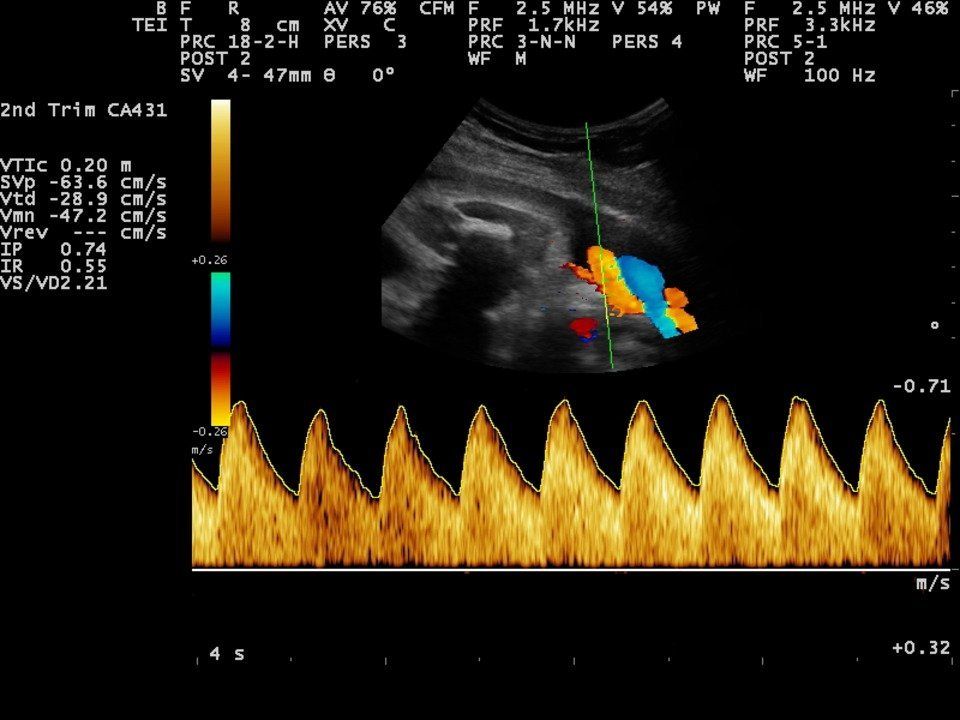

- Umbilical artery Doppler measurement.

- Middle Cerebral Artery Doppler measurement if applicable.